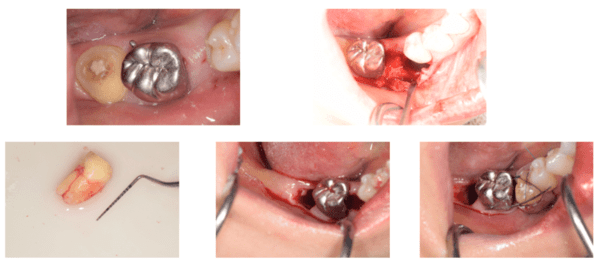

手術前

手術中

説明:

歯ぐきを切り、骨の状態を確認します。移植する歯が入るためのスペースを作るために、骨を歯が入るように削っていきます。

移植する歯

骨のスペースを確保したら移植する歯を抜きます。

移植した歯

移植した歯のレントゲン写真

移植した歯の写真です。隣の歯とワイヤーで固定します。約3週間でワイヤーは外します。

3週間後

3週間後のレントゲン写真

移植後3週間経ったら根管治療を行います。根管治療後はレントゲン撮影をし、お薬がしっかり根の先まで充填できているか確認します。この後、土台をたてて、かぶせ物をかぶせて治療終了です。